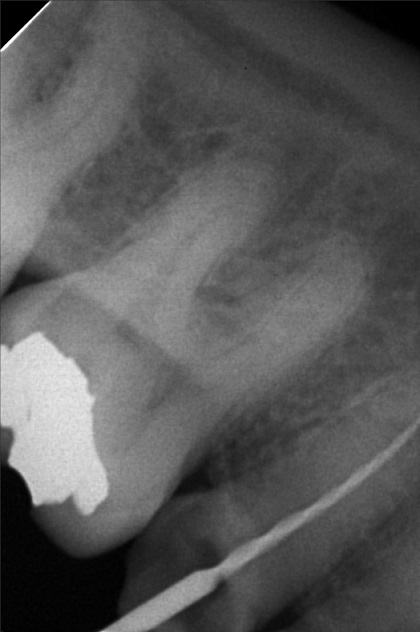

- 9/24/22 - Check up & Xray 10/01/22 - RCT 18mm , formacresol #35 10/08/22- RCT 17mm, campenol 10/15/22- 17.5MM PULP DEVITALIZER PAD done 11/05/22- Zirconia/LC 16 11/19/22- OP/Install Of Crowns